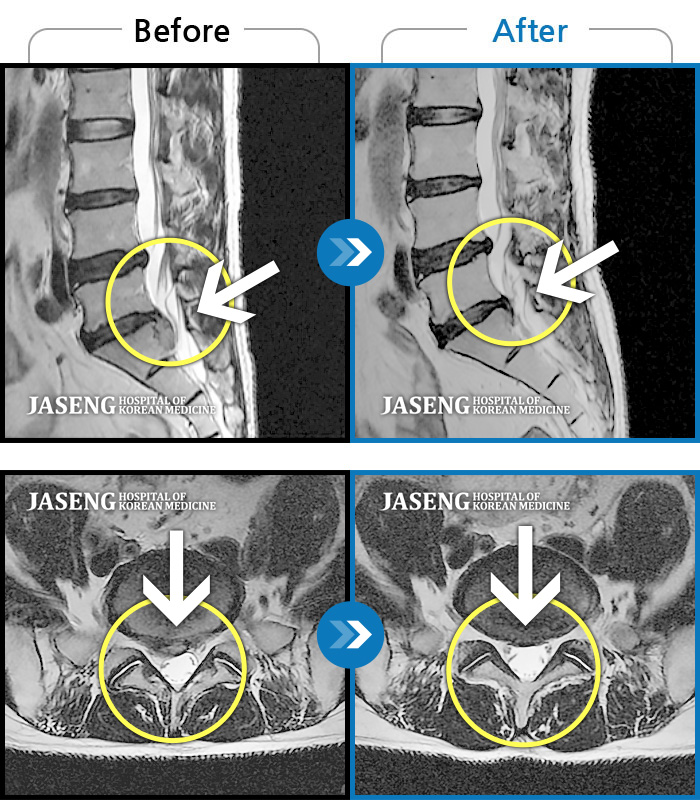

MRI 치료사례

오른쪽 허리 통증, 허리를 숙일 때 다리 당김 증상